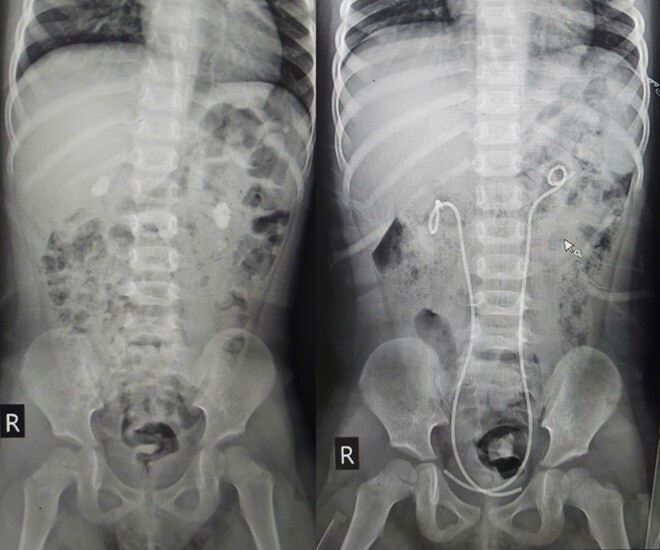

Hình ảnh phim chụp của bệnh nhi trước và sau khi được can thiệp. Ảnh: BSCC.

Gần đây, khi xuất hiện tình trạng bất thường về sức khỏe, bệnh nhi được đưa đến Bệnh viện E thăm khám. Qua các thăm khám lâm sàng và cận lâm sàng, bệnh nhi được xác định bị sỏi thận cả hai bên; trong đó thận trái ứ nước độ 2, thận phải ứ nước độ 1.

Sau hội chẩn, các bác sĩ đã thống nhất phương án tán sỏi qua da. Đây là phương án xử lý tối ưu nhất, ít xâm lấn, khả năng hồi phục nhanh mà vẫn có thể xử lý được sỏi thận cho bệnh nhi. “Trước khi thực hiện can thiệp, chúng tôi đã phải đặt ra bài toán, nên tán sỏi từng bên hay thực hiện đồng thời hai bên cùng một lúc. Sau khi cân nhắc và hội chẩn, các bác sĩ quyết định tán sỏi cả hai bên cùng một lúc để tránh can thiệp, gây mê nhiều lần, giảm đau đớn cho cháu bé”, bác sĩ Liên thông tin.

Sau khi tán sỏi qua da, bệnh nhi an toàn, kết quả kiểm tra cho thấy sỏi hai bên thận đã sạch, đặc biệt cháu bé đã đi lại được chỉ sau 12 tiếng. “Với trường hợp này, chúng tôi đang gửi mẫu sỏi thận đi xét nghiệm để đánh giá nguyên nhân, từ đó có hướng tư vấn, điều trị tiếp theo cho phù hợp”, bác sĩ Liên cho hay.